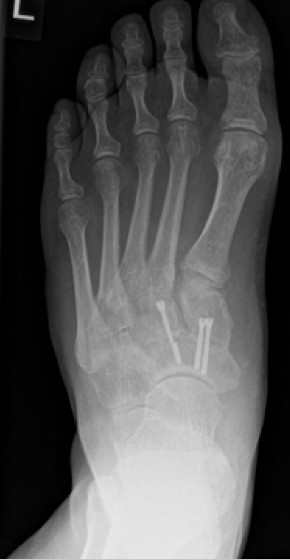

Im Rahmen einer Verlaufskontrolle zeigte sich ein Schraubenbruch als Zeichen einer fehlenden Durchbauung der Arthrodese.

3.- April 2017: Schraubenbruch

Es wurde die Indikation zur Revisionsoperation mit Rearthrodese gestellt. Diese wurde im Juni 2017 durchgeführt.

Die Stabilisierung erfolgte nunmehr mittels Platte und einer externen Zugschraube. Es wurde wiederum Knochenersatzmaterial angelagert.

4.- 06/2017 nach Rearthrodese